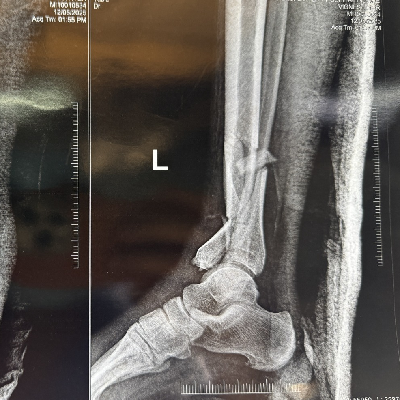

Cavus Foot की सर्जरी के बाद, मरीज अब आराम से चल पा रहा है।

Equino-Cavo-Varus is a complex foot deformity involving high arches, inward heel turning, and toe pointing. Treatment often includes surgery, bracing, or physiotherapy to restore proper alignment and function.